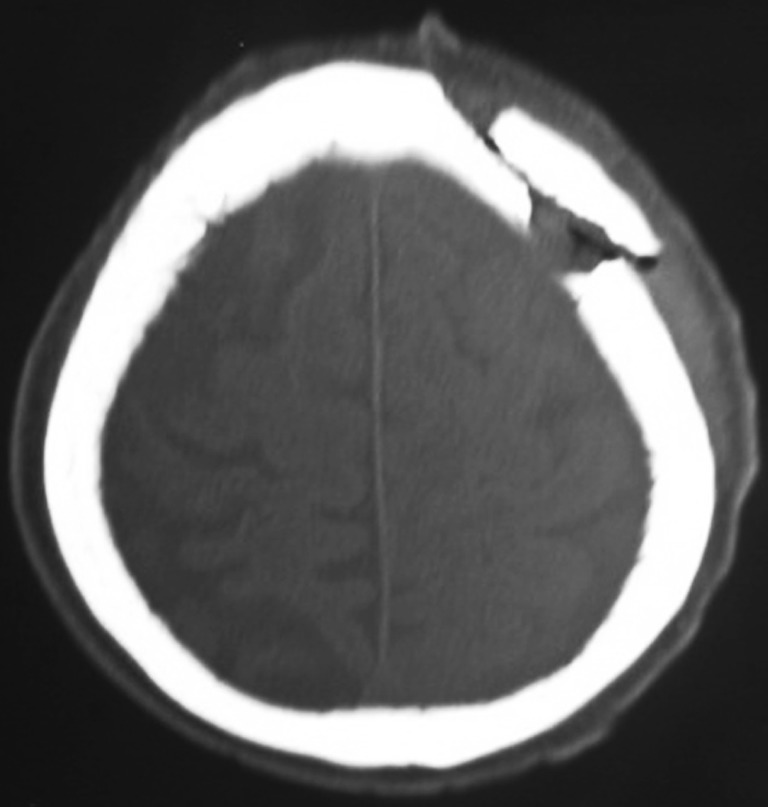

NCCT head is the investigation of choice as in other emergent head injuries (Figs. 2 and 3). It demonstrates the elevation of fractured segment as well as associated underlying intracranial injury and hematomas, all of which are associated with worse prognosis [5–10].

Fig. 3.

Non-contrast computed tomography of head with elevated left frontal skull fragment and underlying contusion